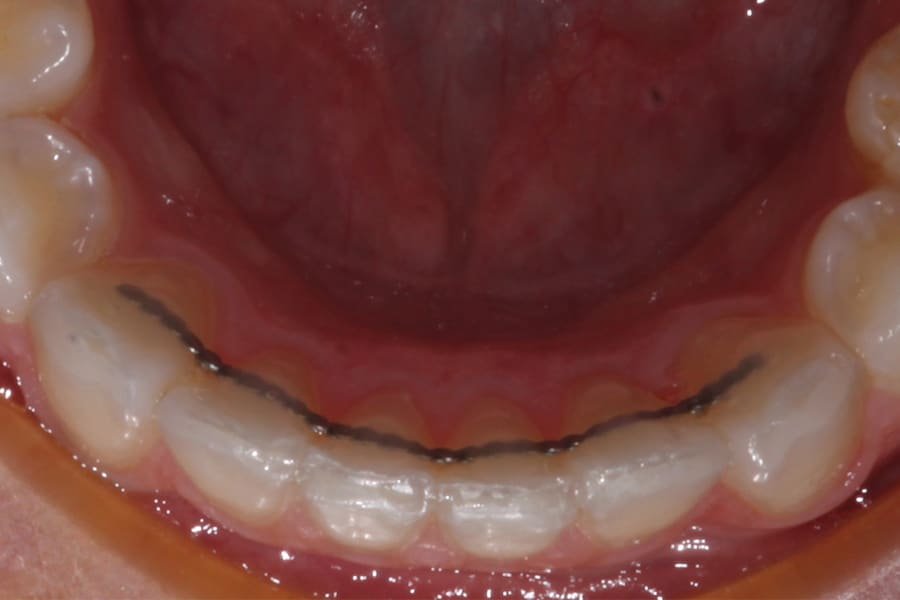

A popular example of this approach is the twisted stainless-steel wire retainer (Figure 1). This design features ease of fabrication and placement as well as minimal cost. Frequently, a twisted lingual retainer can be fabricated chairside and placed immediately with no preparation, impressioning, or laboratory fabrication required. Consequently, this design is commonly utilized. It can be made from a very thin wire (such as a .009" ligature tie) that is folded over and spun down (or twisted) then formed to the arch curvature and direct bonded. Annealing the formed wire prior to placement can be beneficial, as this can remove the "memory" that stainless steel possesses if not permanently deformed.